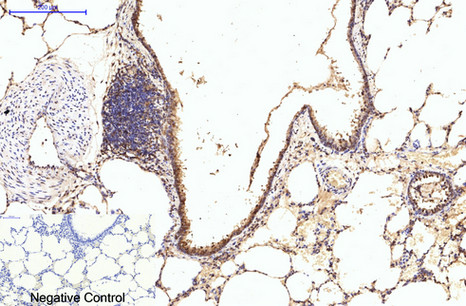

ARG66176 anti-eIF4A1 antibody IHC-P image

Immunohistochemistry: Paraffin-embedded Rat lung tissue stained with ARG66176 anti-eIF4A1 antibody at 1:200 dilution (4°C, overnight). Antigen Retrieval: Boil tissue section in Sodium citrate buffer (pH 6.0) for 20 min.

Negative control was used by secondary antibody only.